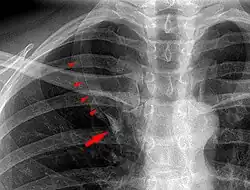

Während normalerweise die Vena azygos unmittelbar am Mediastinum von hinten nach vorne zur Vena cava superior zieht, verläuft sie bei dieser Variante durch den zusätzlichen Lappenspalt bzw. am Boden desselben. Wegen des Verlaufs dieses Azygosseptums von hinten nach vorne ist ein Lobus venae azygos im normalen Röntgenbild des Thorax in der Regel tropfenförmig gut erkennbar, wobei der Bauch des Tropfens der axial getroffenen Vena azygos entspricht.